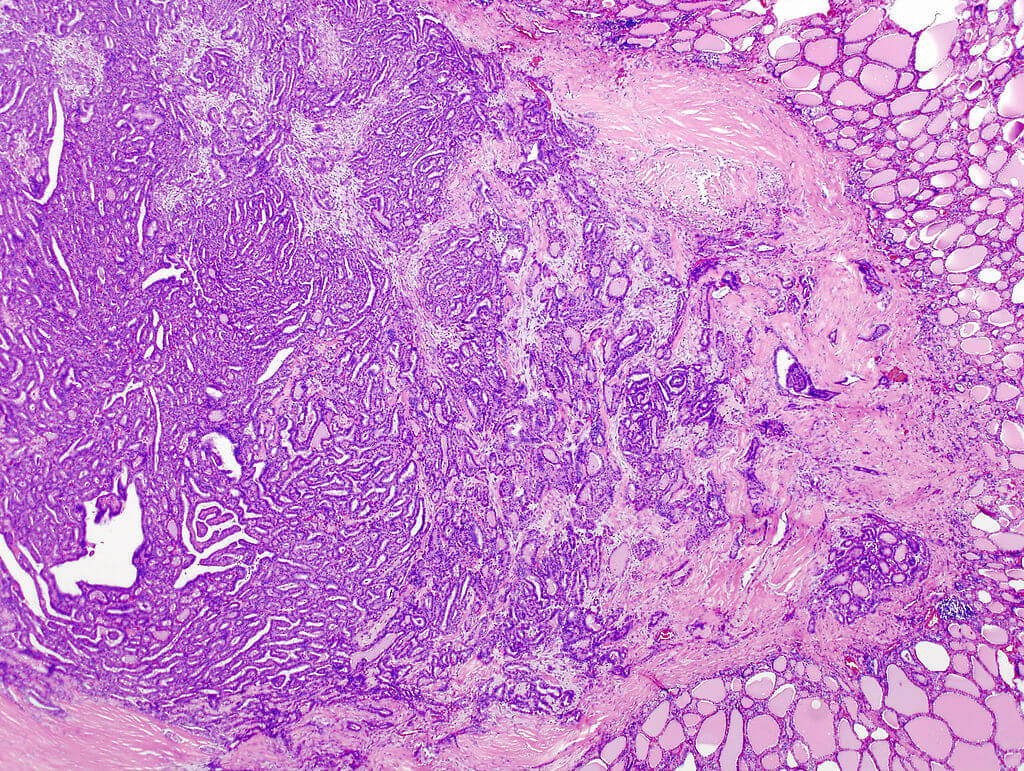

위 쪽의 사진은 갑상선암의 사진입니다. 진한 보라색으로 보이는 부분이 암이고 주변의 정상조직을 파괴하고 있는 모습입니다. 오른쪽 아래와 위쪽 귀퉁이에 분홍색 논 처럼 보이는 것 들이 아직 남아있는 정상 갑상선조직입니다.

암인지 아닌지 현미경을 통해 판단을 내리는데 침윤의 유무는 매우 중요합니다. 다만 특이한 경우가 있는데, 암세포 라고 부를 수 있을 정도로 충분히 심한 변화가 일어난 세포들이 있지만 기저막을 뚫지 못하고 상피세포층 위에만 존재하는 경우를 상피내암(Carcinoma in situ) 라고 합니다. 이렇게 운좋게도 일찍 발견한 경우에는 침윤성 암 보다 상대적으로 치료가 간단하고 경과도 좋은 편입니다.